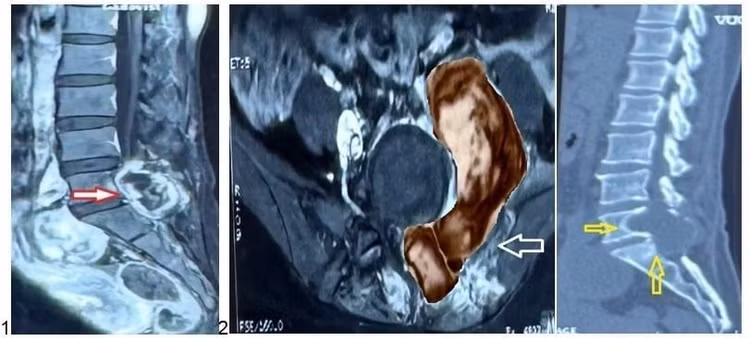

khoi-u-quai.jpg

hình 4 khối u được loại bỏ trong mổ - Ảnh BVCC

Ca mổ kéo dài khoảng ba giờ đồng hồ, khối u được loại bỏ hoàn toàn với lượng máu mất tối thiểu, đánh dấu một ca phẫu thuật thành công và an toàn cho người bệnh.